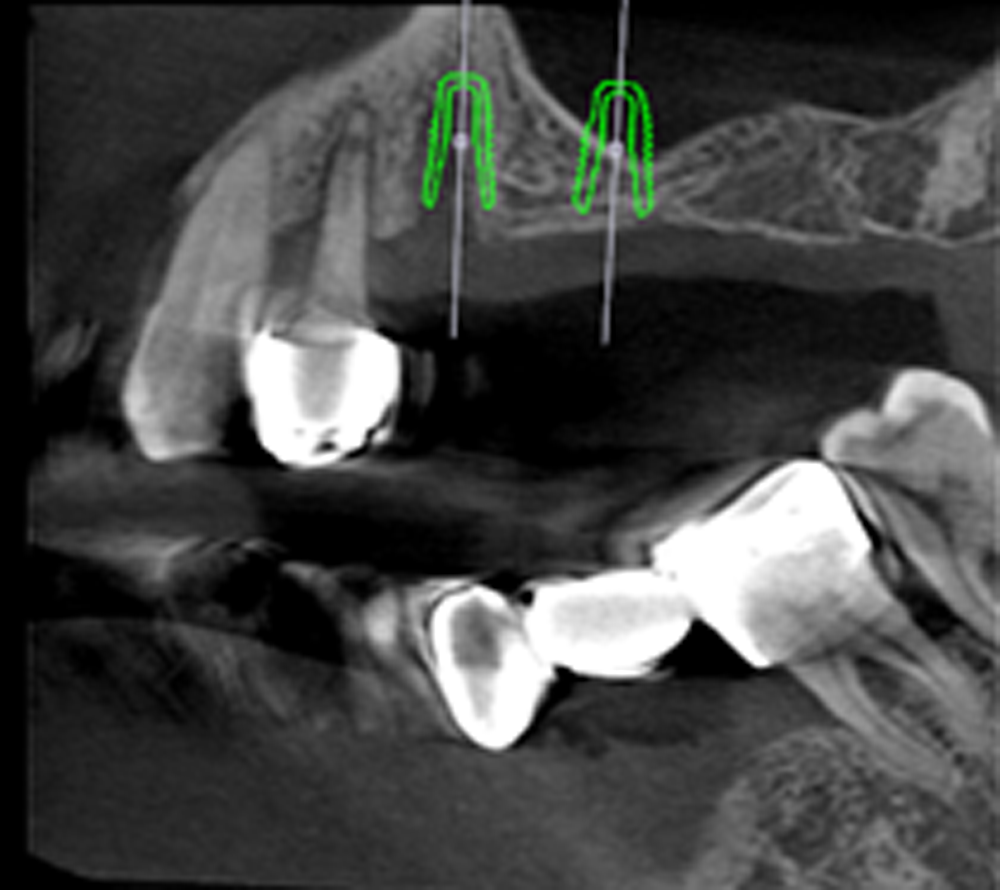

術前利用3D斷層掃描做精準規劃

利用3D斷層掃描及3D口腔掃描儀客製手術導板精準定位